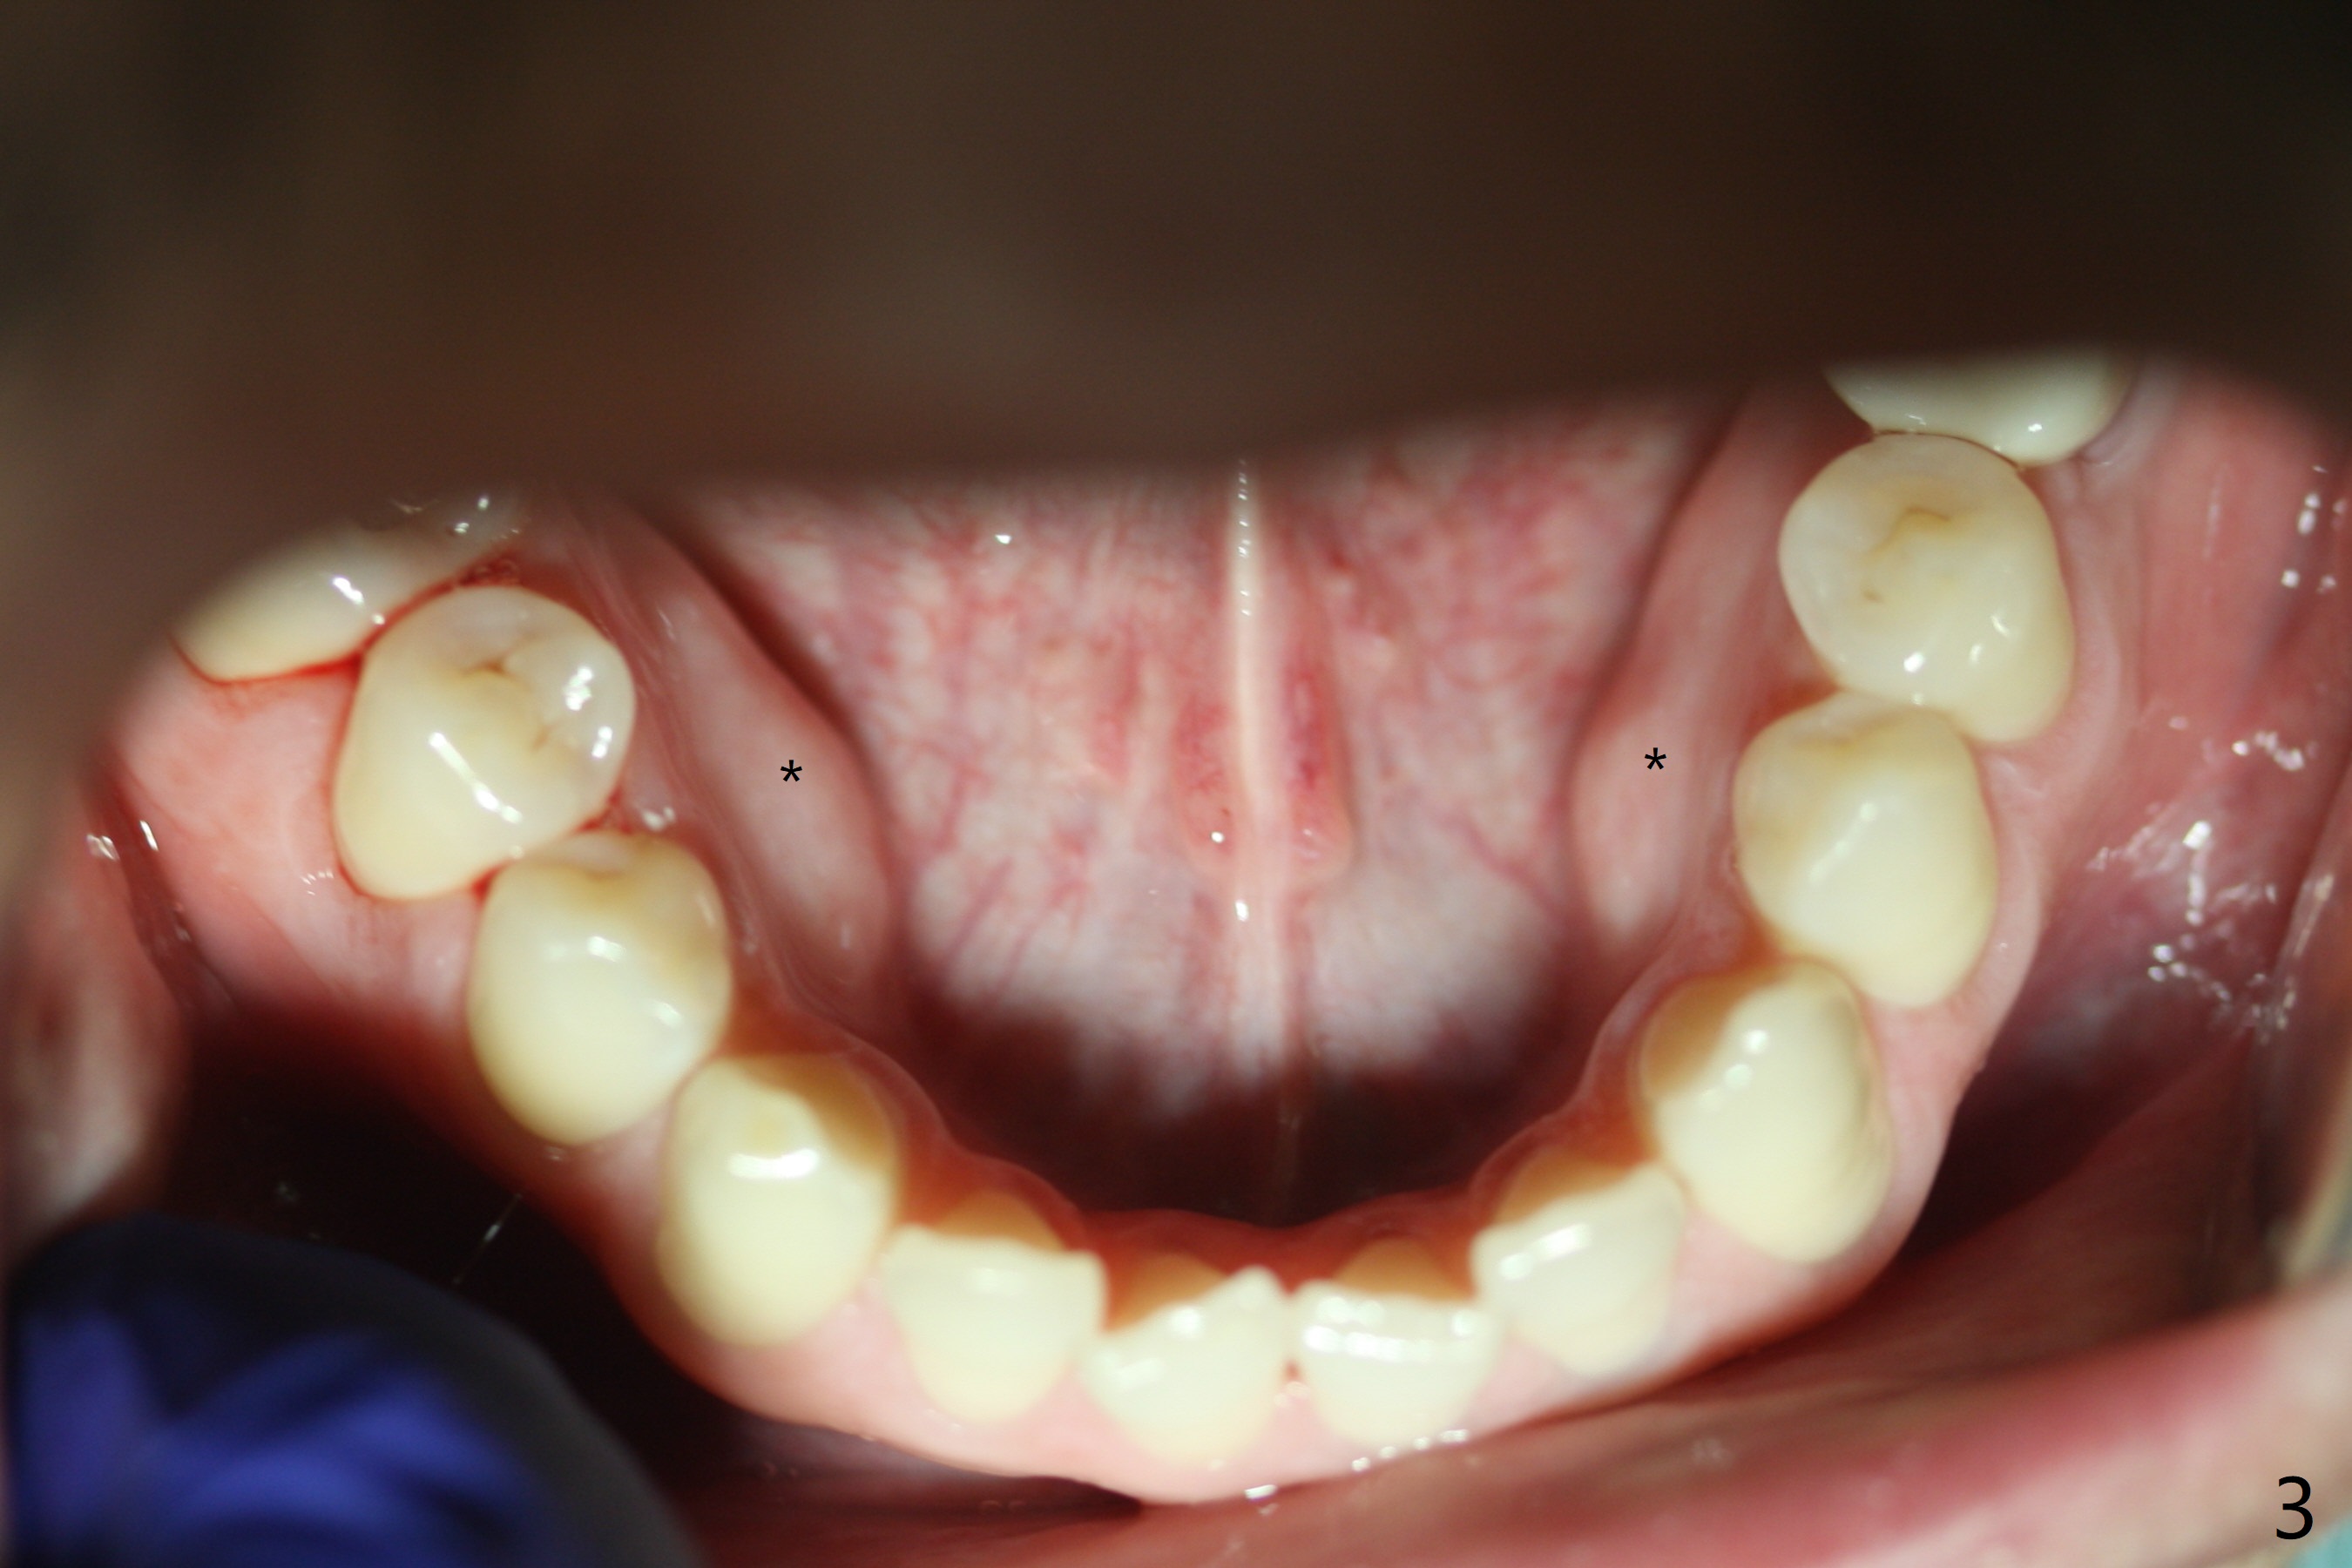

The patient must be a bruxer, as evidenced by tori mandibularis (Fig.3 *), which is related to short crown and dense bone around the coronal end of the implant.